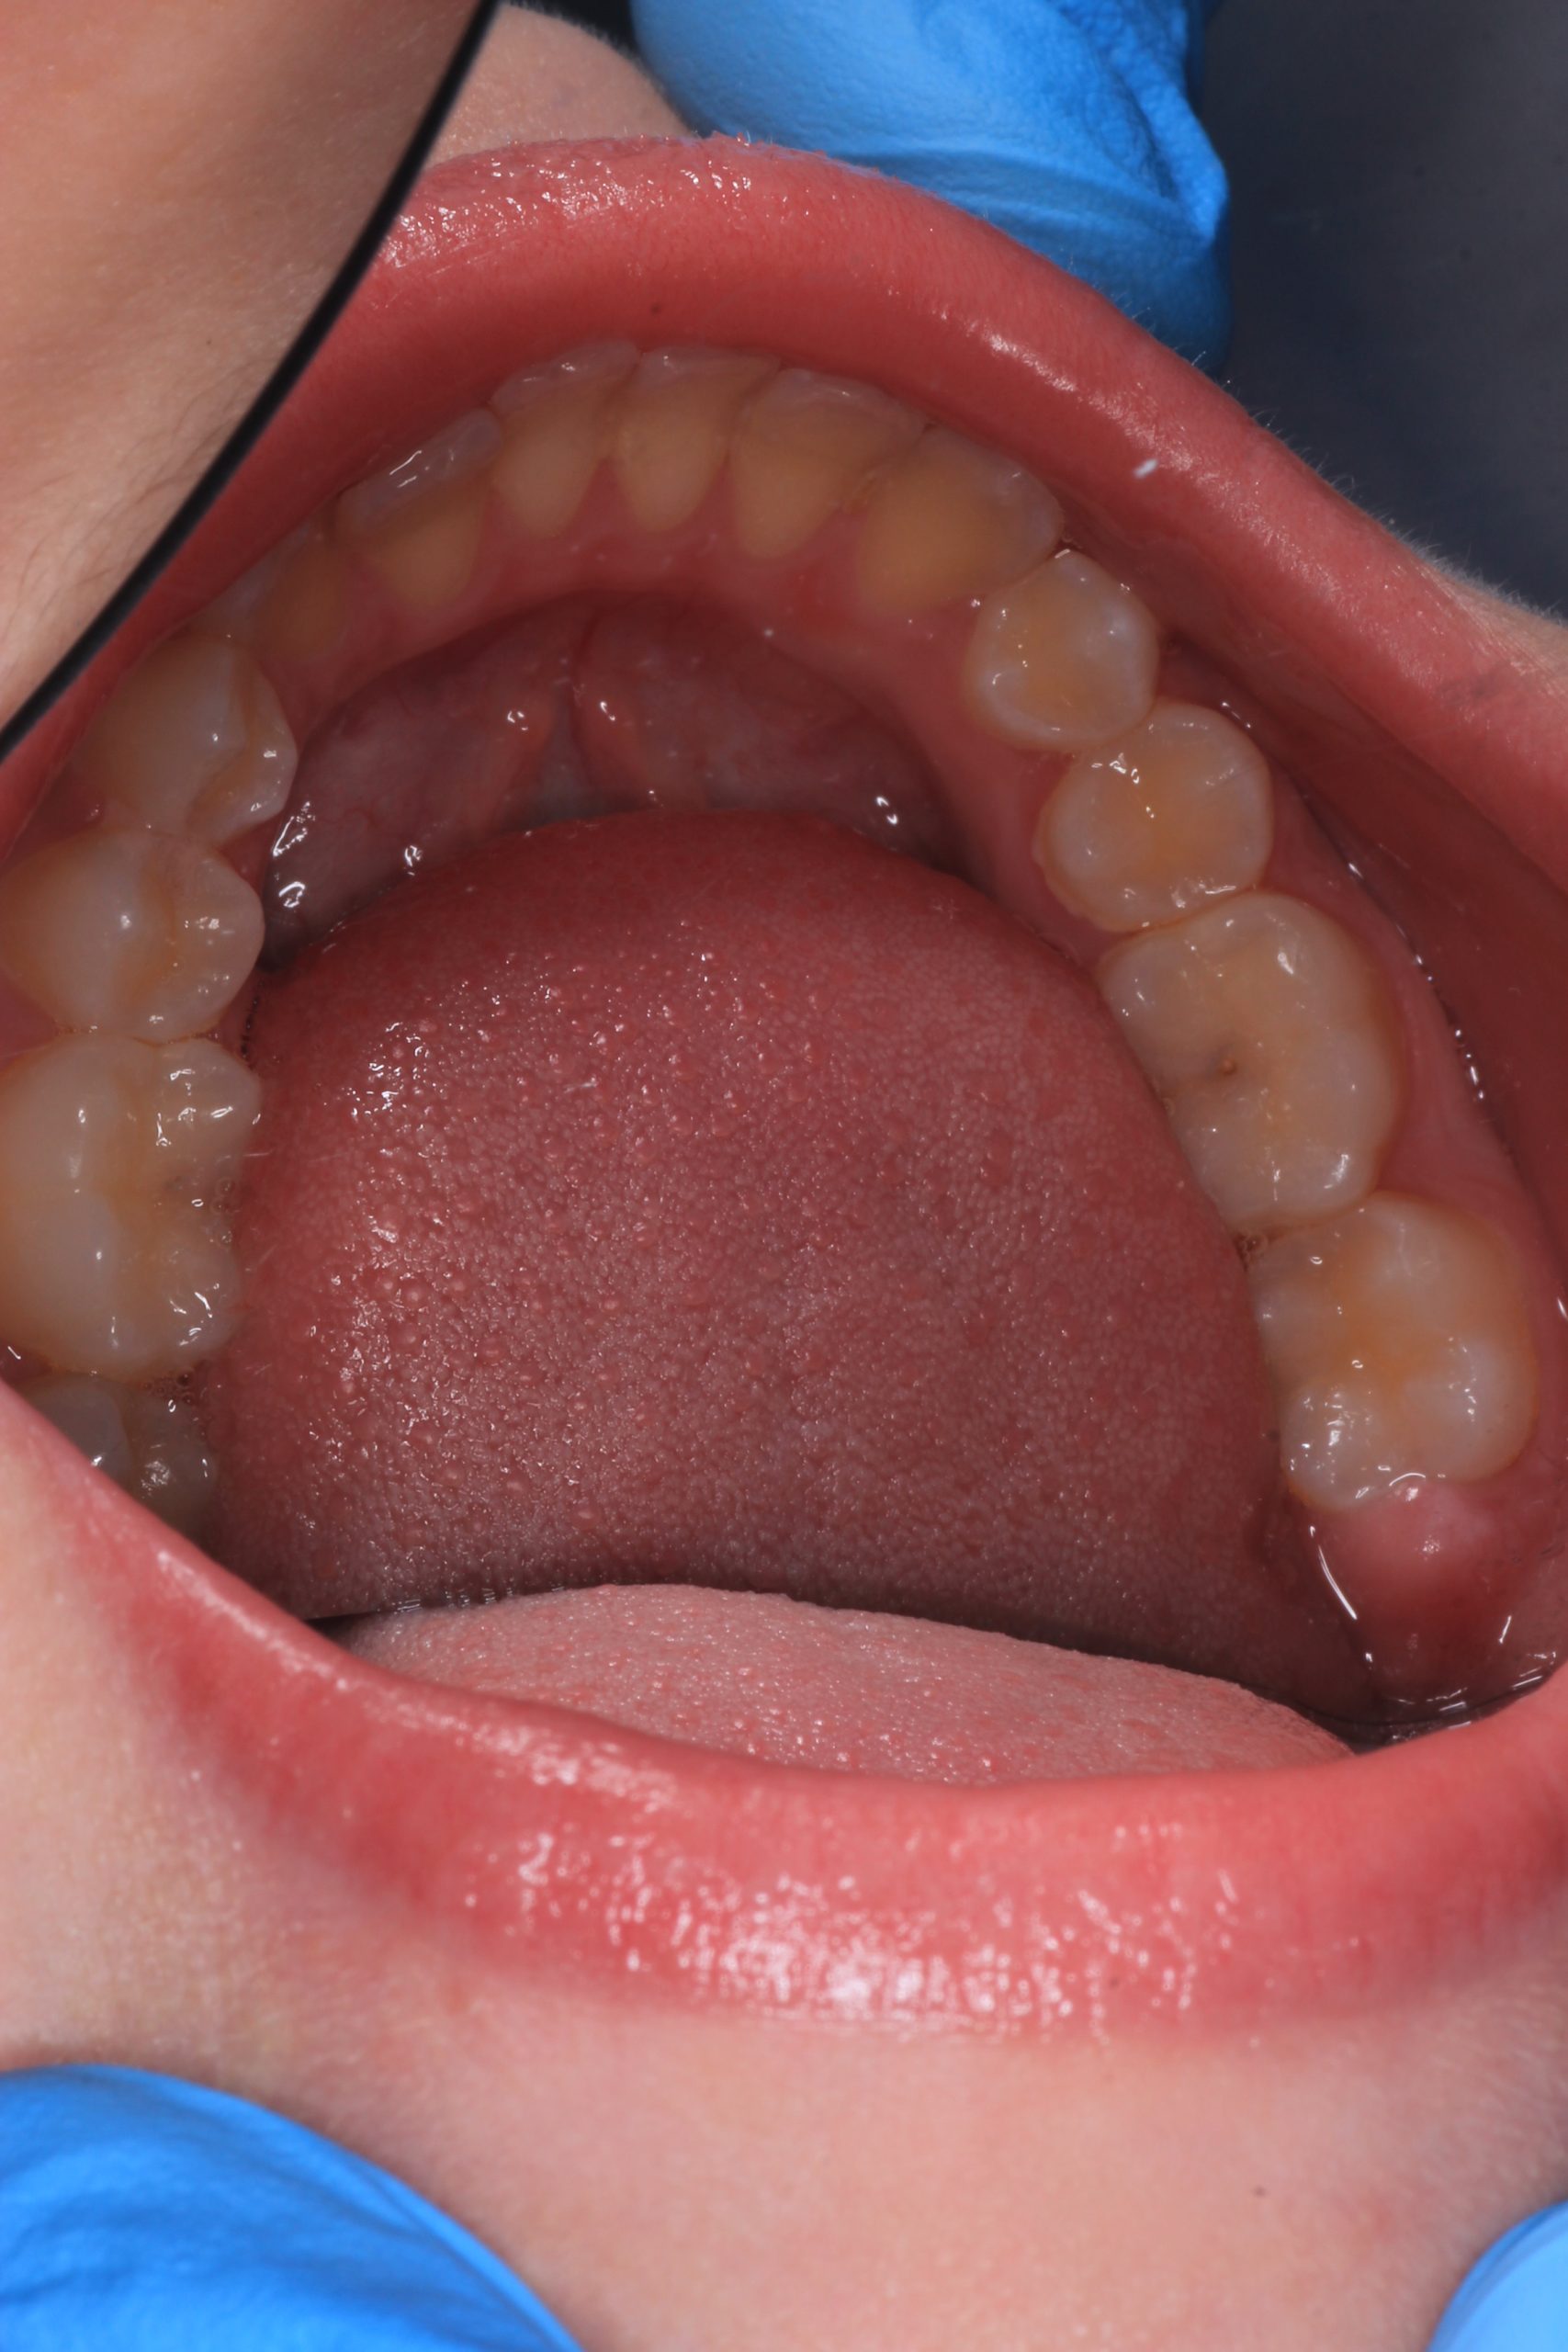

- Detailed Examination

We examine the condition of teeth, gums, and bite. - Plaque Disclosure with Special Indicators